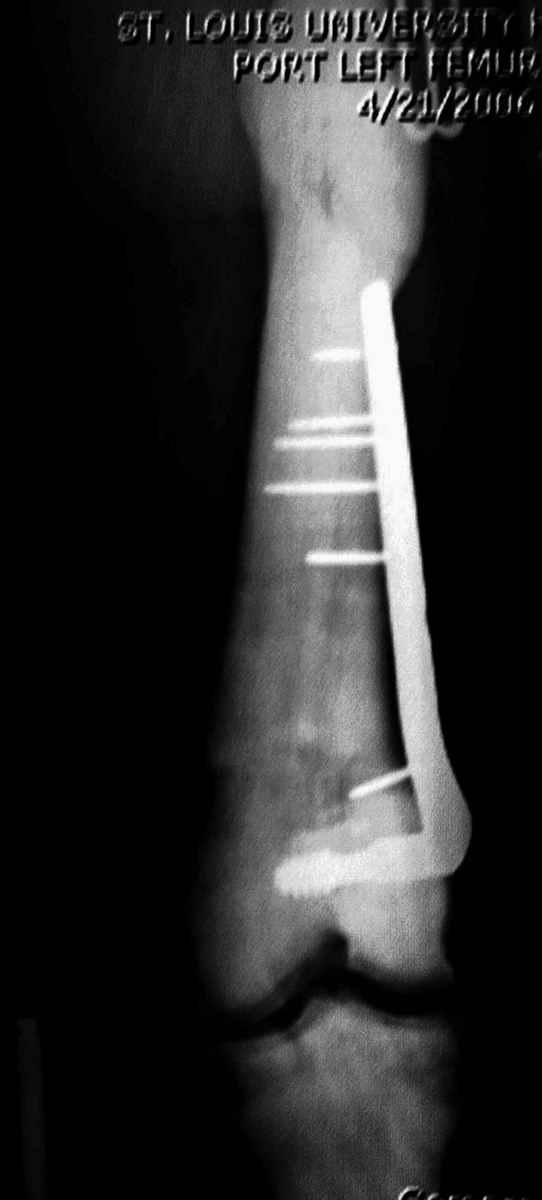

“При лечении переломов у больных с остеопетрозом (в прошлом году был случай) необходимо быть готовым к длительным операциям из-за трудности

обработки традиционными методами "мраморной" кости, иметь в наличие достаточное количество свежих острых инстументов и персонала при необходимости замены (были случаи отстрочки операции на следующий день из-за физической усталости персонала), и надо избежать особо трудоемких операции как интрамедуллярное сверление”.

слайды из прошлегодного случая.